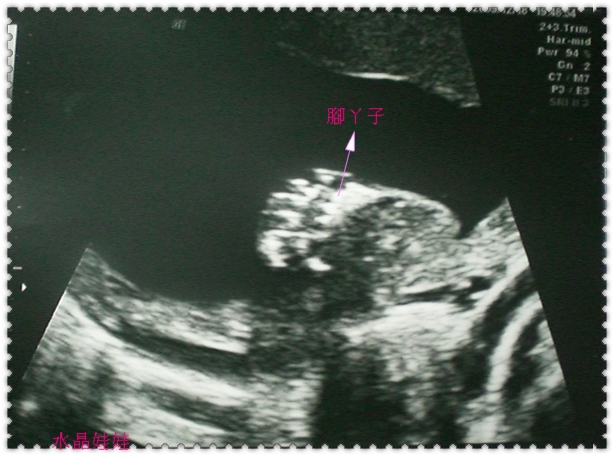

從多錢的頭圍、肚圍、四肢、耳朵、嘴唇、生殖器與蛋蛋、

到腦部、各內臟器官的狀況、血流狀況都檢查過ㄧ次。

兩隻手各五個手指頭、兩隻腳各五個腳指頭、兩個耳朵、嘴唇沒有兔唇,